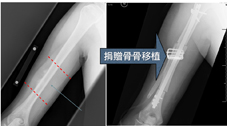

(1) 肢體保留手術目前有兩種方法:一種是將長了腫瘤的關節整個換掉,用訂製型人工關節替代(圖一);另一種是使用他人捐贈的骨骼,取代原來切除的部份(圖二)。

對於骨腫瘤的治療,在近十年來,不管是在診斷方法或是治療方針上,都有相常的進展。如能早期診斷,在種種併發症和功能障礙發生前,予以適當的治療,對於改善病患的治療成果和生治品質,將會有十足的進步。 配合適當骨材, 適當骨移植技術,可以達到肢體保留、和保存肢體原有功能的目標。

圖二、二十四歲男性,患右側肱骨惡性骨肉瘤,經廣泛腫瘤切除,使用他人捐贈之骨骼,重建肢體功能。